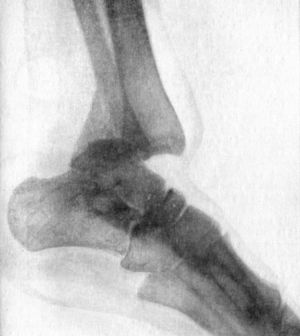

| 99. | Radiogram of Backward Dislocation of Ankle | 195 |